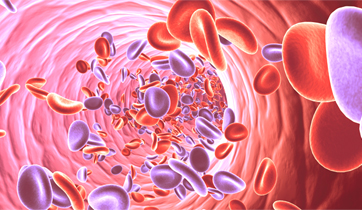

Erectile Dysfunction

Medtronic Corporation

This animationis intended to explain Erectile Dysfunction to physicians. It shows the vessels and nerves involved in blood flow obstruction to the penis, and the erectile tissue's failure to enlarge. The animation also suggests the benefits of clearing the obstruction by using stents.